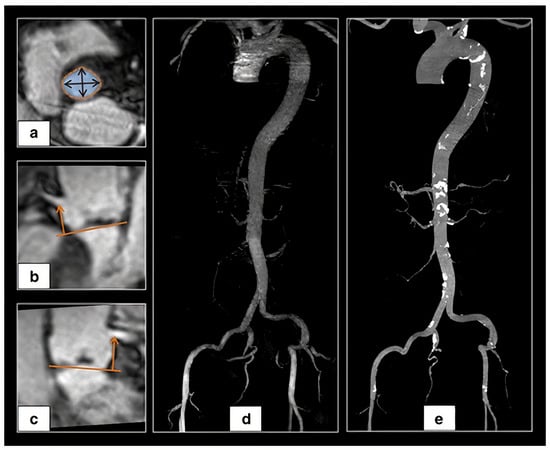

2. Aortic Root Assessment

2.1. Aortic Annulus

2.2. Left Ventricle Outflow Tract (LVOT)

3.2. Available Methods

3.2.1. Manual Sizing

3.2.2. Semi-Automated and Automated Sizing